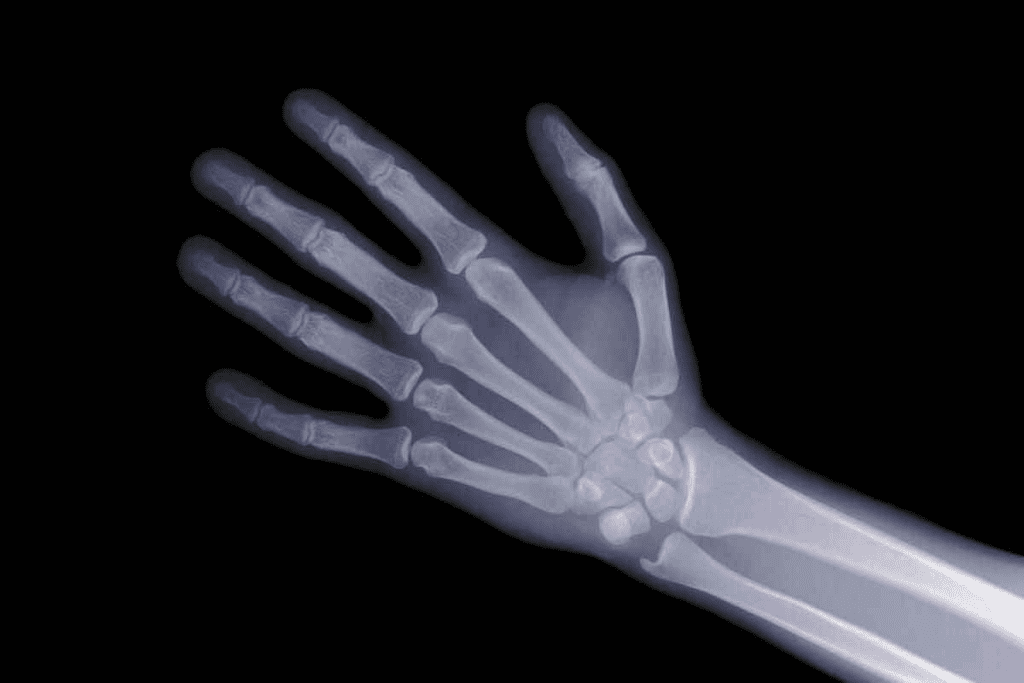

How Technetium-99m Tracers Identify Bone Turnover

A bone scan uses a small amount of radioactive material, like technetium-99m tracers. These tracers attach to bone tissues, showing where bone is growing or repairing.

This attachment lets us see bone metabolism. It shows areas of abnormal bone activity. The more tracer uptake, the more bone turnover there is.